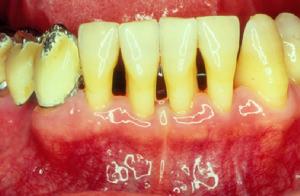

牙結石形成後對人體的危害取決於機體對牙石刺激反應性和修復能力,因此,有的病人表現為牙石的壓迫致牙齦萎縮;而另一些則表現為牙齦受刺激後炎必增生,嚴重的則表現為牙周組織的破壞而發生 牙周病 ,出現牙齦出血、 口臭 、牙周溢膿、牙齒鬆動等改變。

由於牙結石多沉積於牙頸部,若不除去的話,長期刺激牙齦組織,會引起牙齦組織的水腫、充血、齦緣糜爛、牙齦容易出血等一系列牙齦炎的症狀。一些人清晨起床後滿嘴布滿血絲,99%是由牙結石所造成的。如果繼續發展,可造成牙周組織溢膿,出現口臭不適,齒槽骨破壞吸收甚至牙齒鬆動。尤其是兒童,如不注意防止牙齒的形成,成年後極易成為牙周病患者中的一員。所以,牙結石的存在是有害無益的。

沉積在齦緣或齦溝內的結石,對牙齦造成持續性的刺激和壓迫,使牙齦組織發生局部營養障礙,抗菌能力降低,牙齦易出現炎症、出血、萎縮,嚴重時可引發牙周膿腫、牙齒鬆動、脫落,破壞牙列完整,妨礙咀嚼功能,加重消化道負擔,影響機體健康。